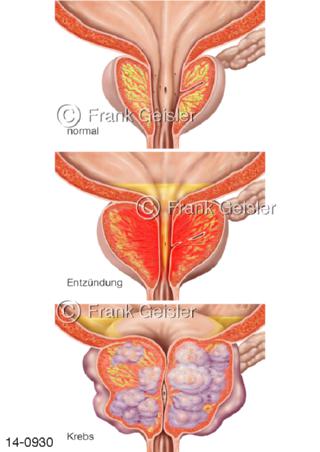

Bildergalerie Urogenitalsystem

Bilder zum Urogenitalsystem mit Urogenitalorgane, Urogenitaltrakt, zum Harn- und Geschlechtsapparat, Harnorgane und Geschlechtsorgane, Organe der Harnwege und der Fortpflanzung, Harnorgane und Geschlechtsorgane im männlichen und weiblichen Urogenitalsystem